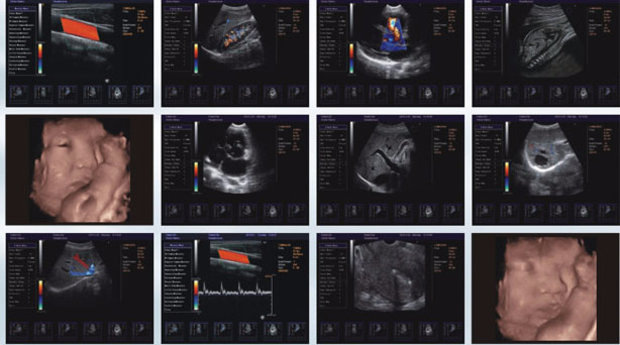

Что показывает УЗИ?

На 3 скрининге врач оценивает состояние матери и плода:

• плацента и ее характеристики (зрелость, толщина, место прикрепления);

• состояние цервикального канала, его размеры;

• состояние матки и придатков;

• околоплодные воды (их количество);

• пуповина;

• строение черепа (лицевой части) плода;

• позвоночник;

• внутренние органы и системы плода (брюшная полость, сердце и магистральные сосуды, кровоснабжающие его, мочеполовая система);

• состояние структур головного мозга и кровоток в галеновой вене.

Кроме того, определяют расположение плода, а также предлежание и отсутствие/наличие обвития пуповинными кольцами.

Усредненные нормативы показателей плода (32-34 недели):

• ЛЗР (лобно-затылочный) размер около от 102 до 107 мм;

• БПР (бипариетальный) размер от 85 до 89 мм;

• ОГ от 309 до 323 мм;

• ОЖ от 266 до 285 мм;

• предплечье от 46 до 55 мм;

• кости голени от 52 до 57 мм;

• бедро от 62 до 66 мм;

• плечо от 55 до 59 мм;

• рост ребенка от 43 до 47 см;

• вес плода от 1790 до 2390 граммов.

Показатели плаценты по УЗИ:

• толщина от 25,3 до 41,6 мм. на 32-й нед. (от 26,8 до 43,8 мм. на 34-й нед.);

• степень зрелости - I-II;

• АИ (амниотический индекс) от 81 до 278 мм;

• шейка матки не менее 30 мм, зев закрыт.